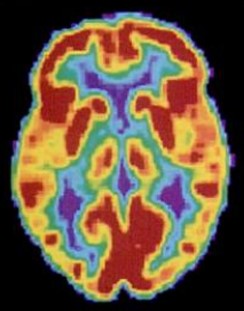

陽電子放出断層撮影Positron emission tomography(PET)スキャン

脳のさまざまな部分の活動を示すことができる。トレーサーと呼ばれる軽度の放射性物質を飲んだり注射したりする。脳の領域がより活発になるにつれて、より多くの血液がその領域に流れるため、トレーサーの動きを監視し、特定の行動中の脳のアクティブ領域と非アクティブ領域の大まかなマップを作成することができる。

PETスキャンでは詳細が分からず、脳の中で起きている出来事を知ることも出来ず、さらに脳が放射線にさらされるリスクがあるためfMRIに置き換えられてきた。ただし、CTと組み合わせると、PETテクノロジーは神経伝達物質受容体の活動のより良いイメージングを可能にし、統合失調症の研究に使用されている。